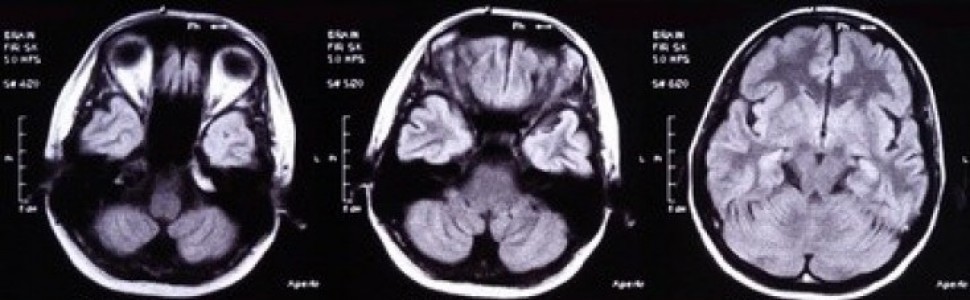

Podstawowymi argumentami w dyskusji na temat związku bądź odrębności ADEM i stwardnienia rozsianego są długofalowe badania katamnestyczne przypadków ADEM pod kątem czy po przebyciu ostrego epizodu choroby następuje trwałe wyleczenie, czy też przeciwnie – po krótszym lub dłuższym czasie – rozwija się typowy przebieg stwardnienia rozsianego. Z dyskusji należy wyłączyć przypadki izolowanych uszkodzeń demielinizacyjnych ośrodkowego układu nerwowego, które w łączności z wieloogniskowymi zmianami w obrazie rezonansu magnetycznego traktowane są jako pierwszy rzut stwardnienia rozsianego.